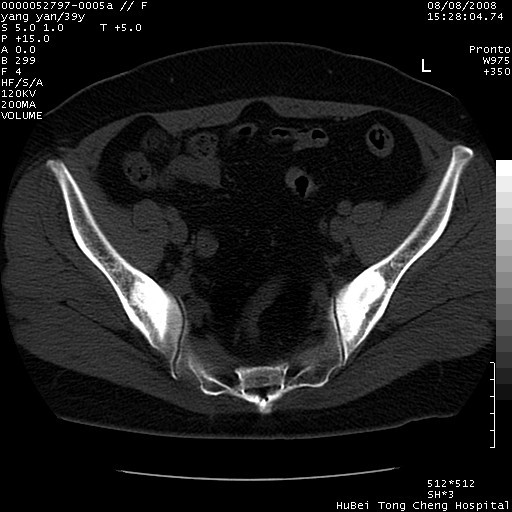

患者 女,39岁。因外伤检查,偶然发现。

典型!双侧骶髂关节致密性骨炎。

典型!病变主要累及双侧髂骨。常见于育龄期妇女。

致密性骨炎,一般不跨越关节面,可是这个骶骨关节面也有硬化。

髂骨致密性骨炎系一种以骨质硬化为特点的非特异性炎症,有高度致密的骨硬化现象,尤其以髂骨下2/3更为明显,但关节间隙则无改变。因位于骶髂关节,且该关节症状明显,故又称之为“骶髂关节致密性骨炎”。 本病90%以上为中年女性,以妊娠后期、尤其分娩后为多见,亦可见于尿路或女性附件慢性感染后,或盆腔内其他感染。此外,臀骶部的外伤亦可诱发或引起本病。  妊娠、分娩及外伤均可引起骶髂关节韧带的撕裂而易使局部的血供受阻。因此早期局部呈现充血、水肿及渗出增加等,渐而局部出现增生与变性反应,随着胶原纤维的致密化而向硬化演变;血管形成厚壁血管,易闭塞而引起髂骨耳状面处缺血和缺氧,骨质呈现硬化性改变,以致手术时局部出血较少。骶髂关节囊壁显示纤维增生、弹性降低及松动样改变。继发于盆腔内炎症者亦出现相类似的病理改变,可能系细菌内毒素作用所致。